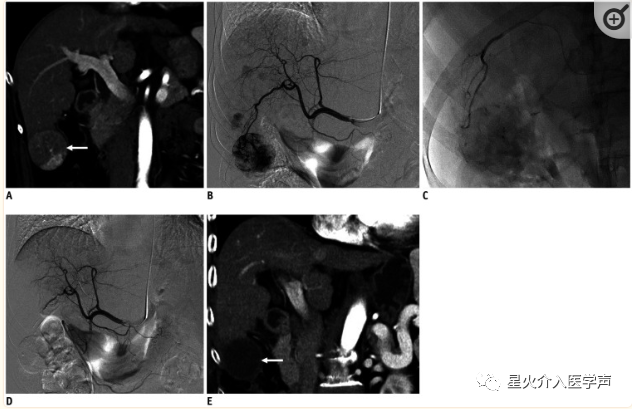

1.经桡肝动脉化疗栓塞术

采用上述标准技术建立桡动脉通路,使用5Fr桡动脉鞘。在DSA引导下,将0.035英寸的Glidewire(长度为150-230 cm)和5F肝管同轴推进至降主动脉,并对腹腔干、肝动脉和肠系膜上动脉进行选择性血管造影。超选择性导管插入术使用微导管(长度135或150 cm;直径1.9–2.8 Fr)。TACE使用碘油乳剂(lipiodol Ultra-Fluid,加栢公司)和盐酸多柔比星,然后给予混合有造影剂的明胶海绵颗粒(150-350μm)栓塞,直至肿瘤供血动脉血流淤滞(图7).Pua等人(30)报告,在经TRA入路TACE期间,使用锥形束CT检查(100%成功率)。盐泽等人(29)回顾性比较了TRA与TFA在肝动脉内治疗中的作用,并显示出相当的有效性(TRA的技术成功率为98.3%)。Yamada et al.(8)和Hung et al.(12)认为,TRA是大多数患者的首选入路,可减少医生的辐射暴露。Iezzi等(13)进行的另一项前瞻性单中心研究表明,所有患者(100%)成功经TRA入路进行肝脏化疗栓塞。没有从桡动脉入路转换为股动脉入路的病例(交叉率:0%)。TRA治疗需要更长的准备时间(p < 0.008);TRA手术的特点还包括穿刺、透视和总检查时间更长,平均辐射剂量和使用的造影剂体积更高,尽管这些差异没有统计学意义。

桡动脉鞘怎么读经桡动脉通路外周介入治疗最新综述_https://www.jmylbn.com_新闻资讯_第9张

图7:TRA在经桡肝动脉化疗栓塞术中的应用。

A.冠状位增强CT示肝6段5 cm肝细胞癌(箭头)。B.肝动脉造影示肝两叶多发富血供肿瘤。C.使用微导管选择肿瘤供血血管后,缓慢注射载多柔比星/非离子型造影剂混悬液的药物洗脱微球,直至接近停滞。D.栓塞后肝动脉造影显示肝脏肿瘤血管完全阻断。E. TACE术后1个月冠状位增强CT图像显示肿瘤完全缓解(箭头)。TRA = 经桡动脉入路,TACE = 经动脉化疗栓塞。

最近,TRA也被用于肝恶性肿瘤的放射栓塞治疗,患者对TRA表现出强烈的偏好,放射剂量、透视时间或操作相关并发症无显著差异(7,15)。